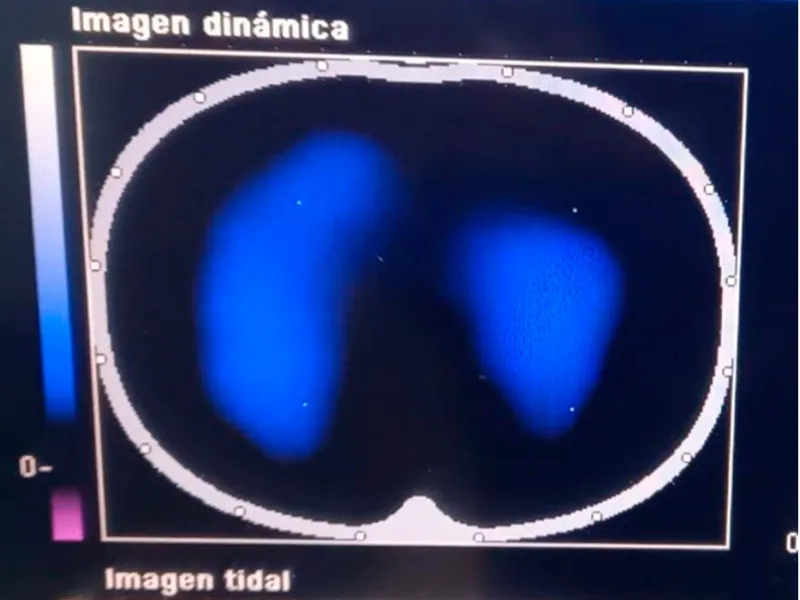

Imágenes de tomografía que se toman para analizar el desempeño de la fisioterapia con el incentivo de re-expansión pulmonar. El área de color azul-blanco representa el volumen del pulmón en un corte transversal, visto desde arriba, cuanto mayor aire llega a los pulmones se expande el pulmón y llega aire a zonas al pulmón que originalmente no se utilizaban.

Imágenes de tomografía que se toman para analizar el desempeño de la fisioterapia con el incentivo de re-expansión pulmonar. El área de color azul-blanco representa el volumen del pulmón en un corte transversal, visto desde arriba, cuanto mayor aire llega a los pulmones se expande el pulmón y llega aire a zonas al pulmón que originalmente no se utilizaban.

Imágenes de tomografía que se toman para analizar el desempeño de la fisioterapia con el incentivo de re-expansión pulmonar. El área de color azul-blanco representa el volumen del pulmón en un corte transversal, visto desde arriba, cuanto mayor aire llega a los pulmones se expande el pulmón y llega aire a zonas al pulmón que originalmente no se utilizaban.